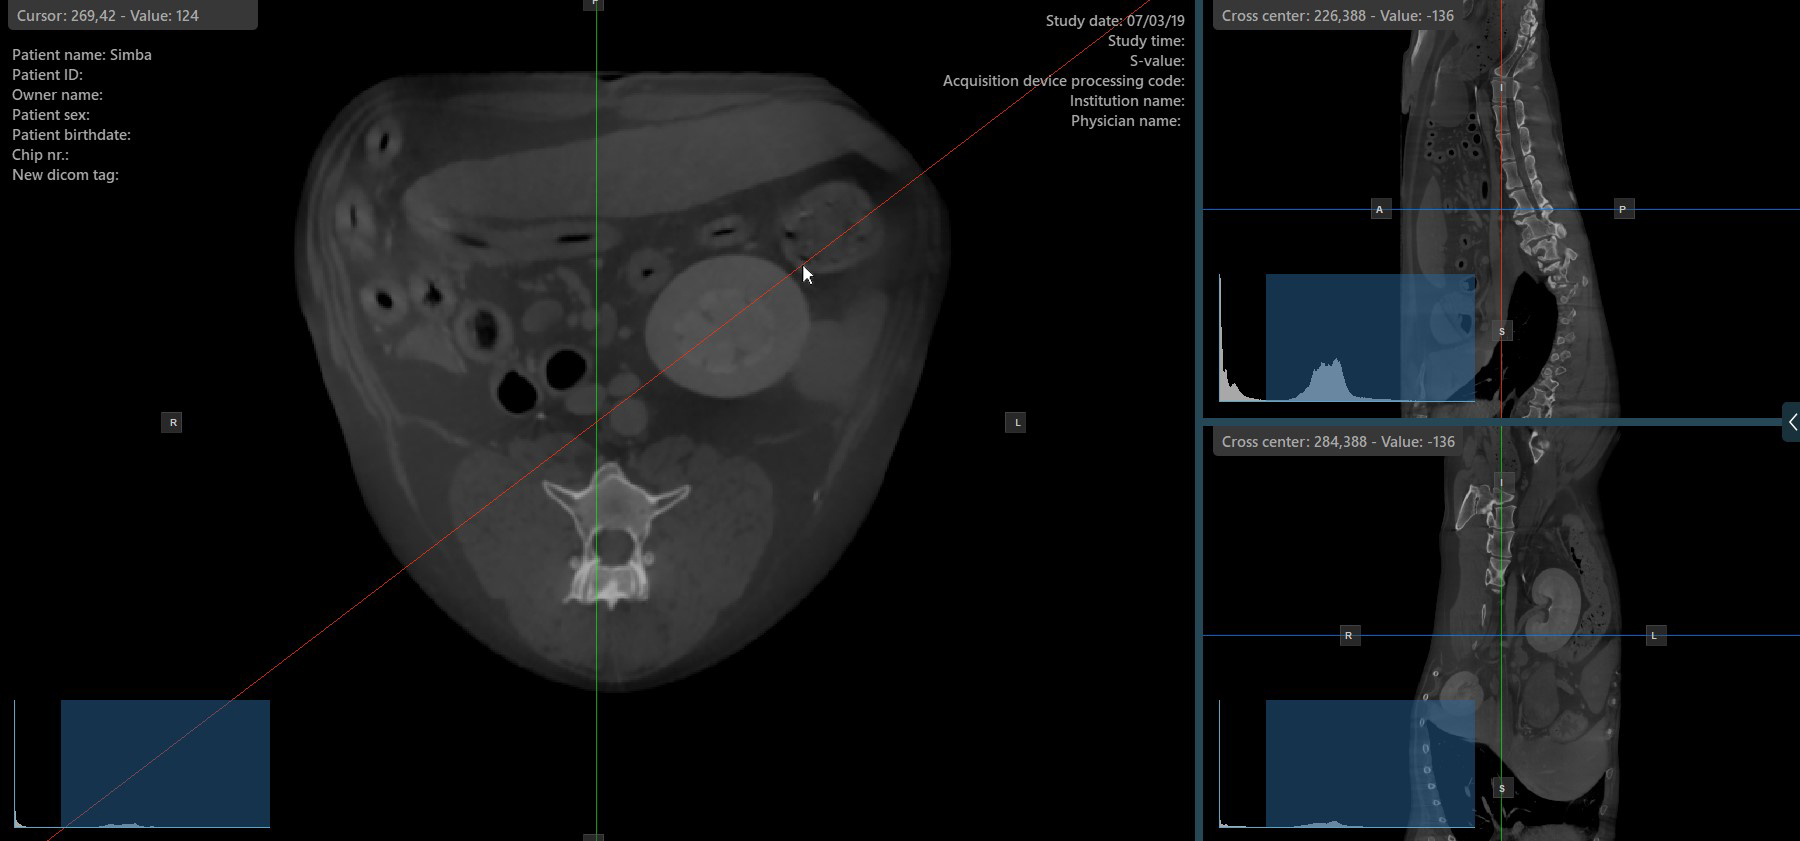

Change Slicer Rotation¶

Altering the rotation of a slicer will change the orientation of the corresponding image planes. Individual slicers can be selected by using the Select Item (Default) tool, assigned to the right mouse button by default.

Once the specific slicer is selected, drag the slicer in the desired direction to rotate it. The corresponding image plane’s orientation changes accordingly.

By default, each slicer can be rotated separately. The corresponding icon in the left toolbar of the CT Viewer will be deselected when the slicers are rotated individually.